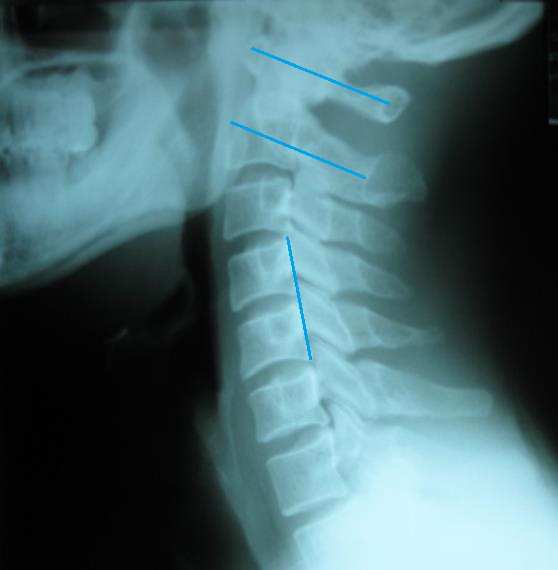

진단 : 요통과 관련한 척추문제는 해결한 상태였으나 어깨 검사를 해보니 좌측 어깨의 회전 범위가 많이 감소된 상태였고 근육적인 문제가 약간 보이긴 하나 그리 심하지는 않은 상태였습니다. 다시 척추문제를 재검 해 보니 흉추의 문제가 남아 있었습다. 이 후 1-2회 흉추 치료를 하였고 치료 후 어깨 운동 범위가 많이 개선되었다고 평상시 본인은 어깨가 아픈지 몰랐는데 치료 받고 보니 어깨가 많이 가벼워졌다고 좋아하셨습니다. 수 개월 후 발목 염좌로 내원하였고 어깨 문제를 재검해보니 별 문제는 없었으며 골프도 시원스럽게 잘 쳐진다고 만족해 하셨습니다.